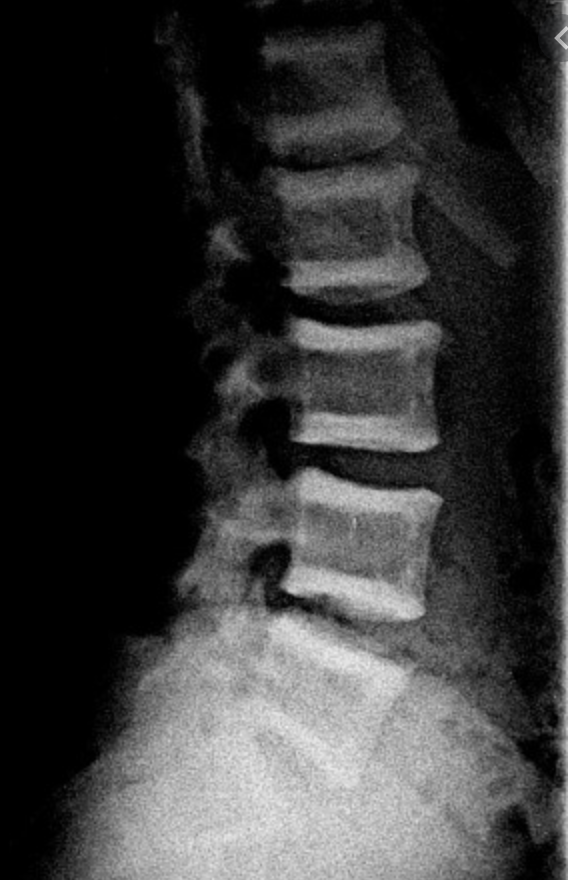

X-Ray changes in renal bone disease?

“rugger jersey” appearance of spine - denser white at both ends of vertebra (sclerosis) and less white in centre (osteomalacia)